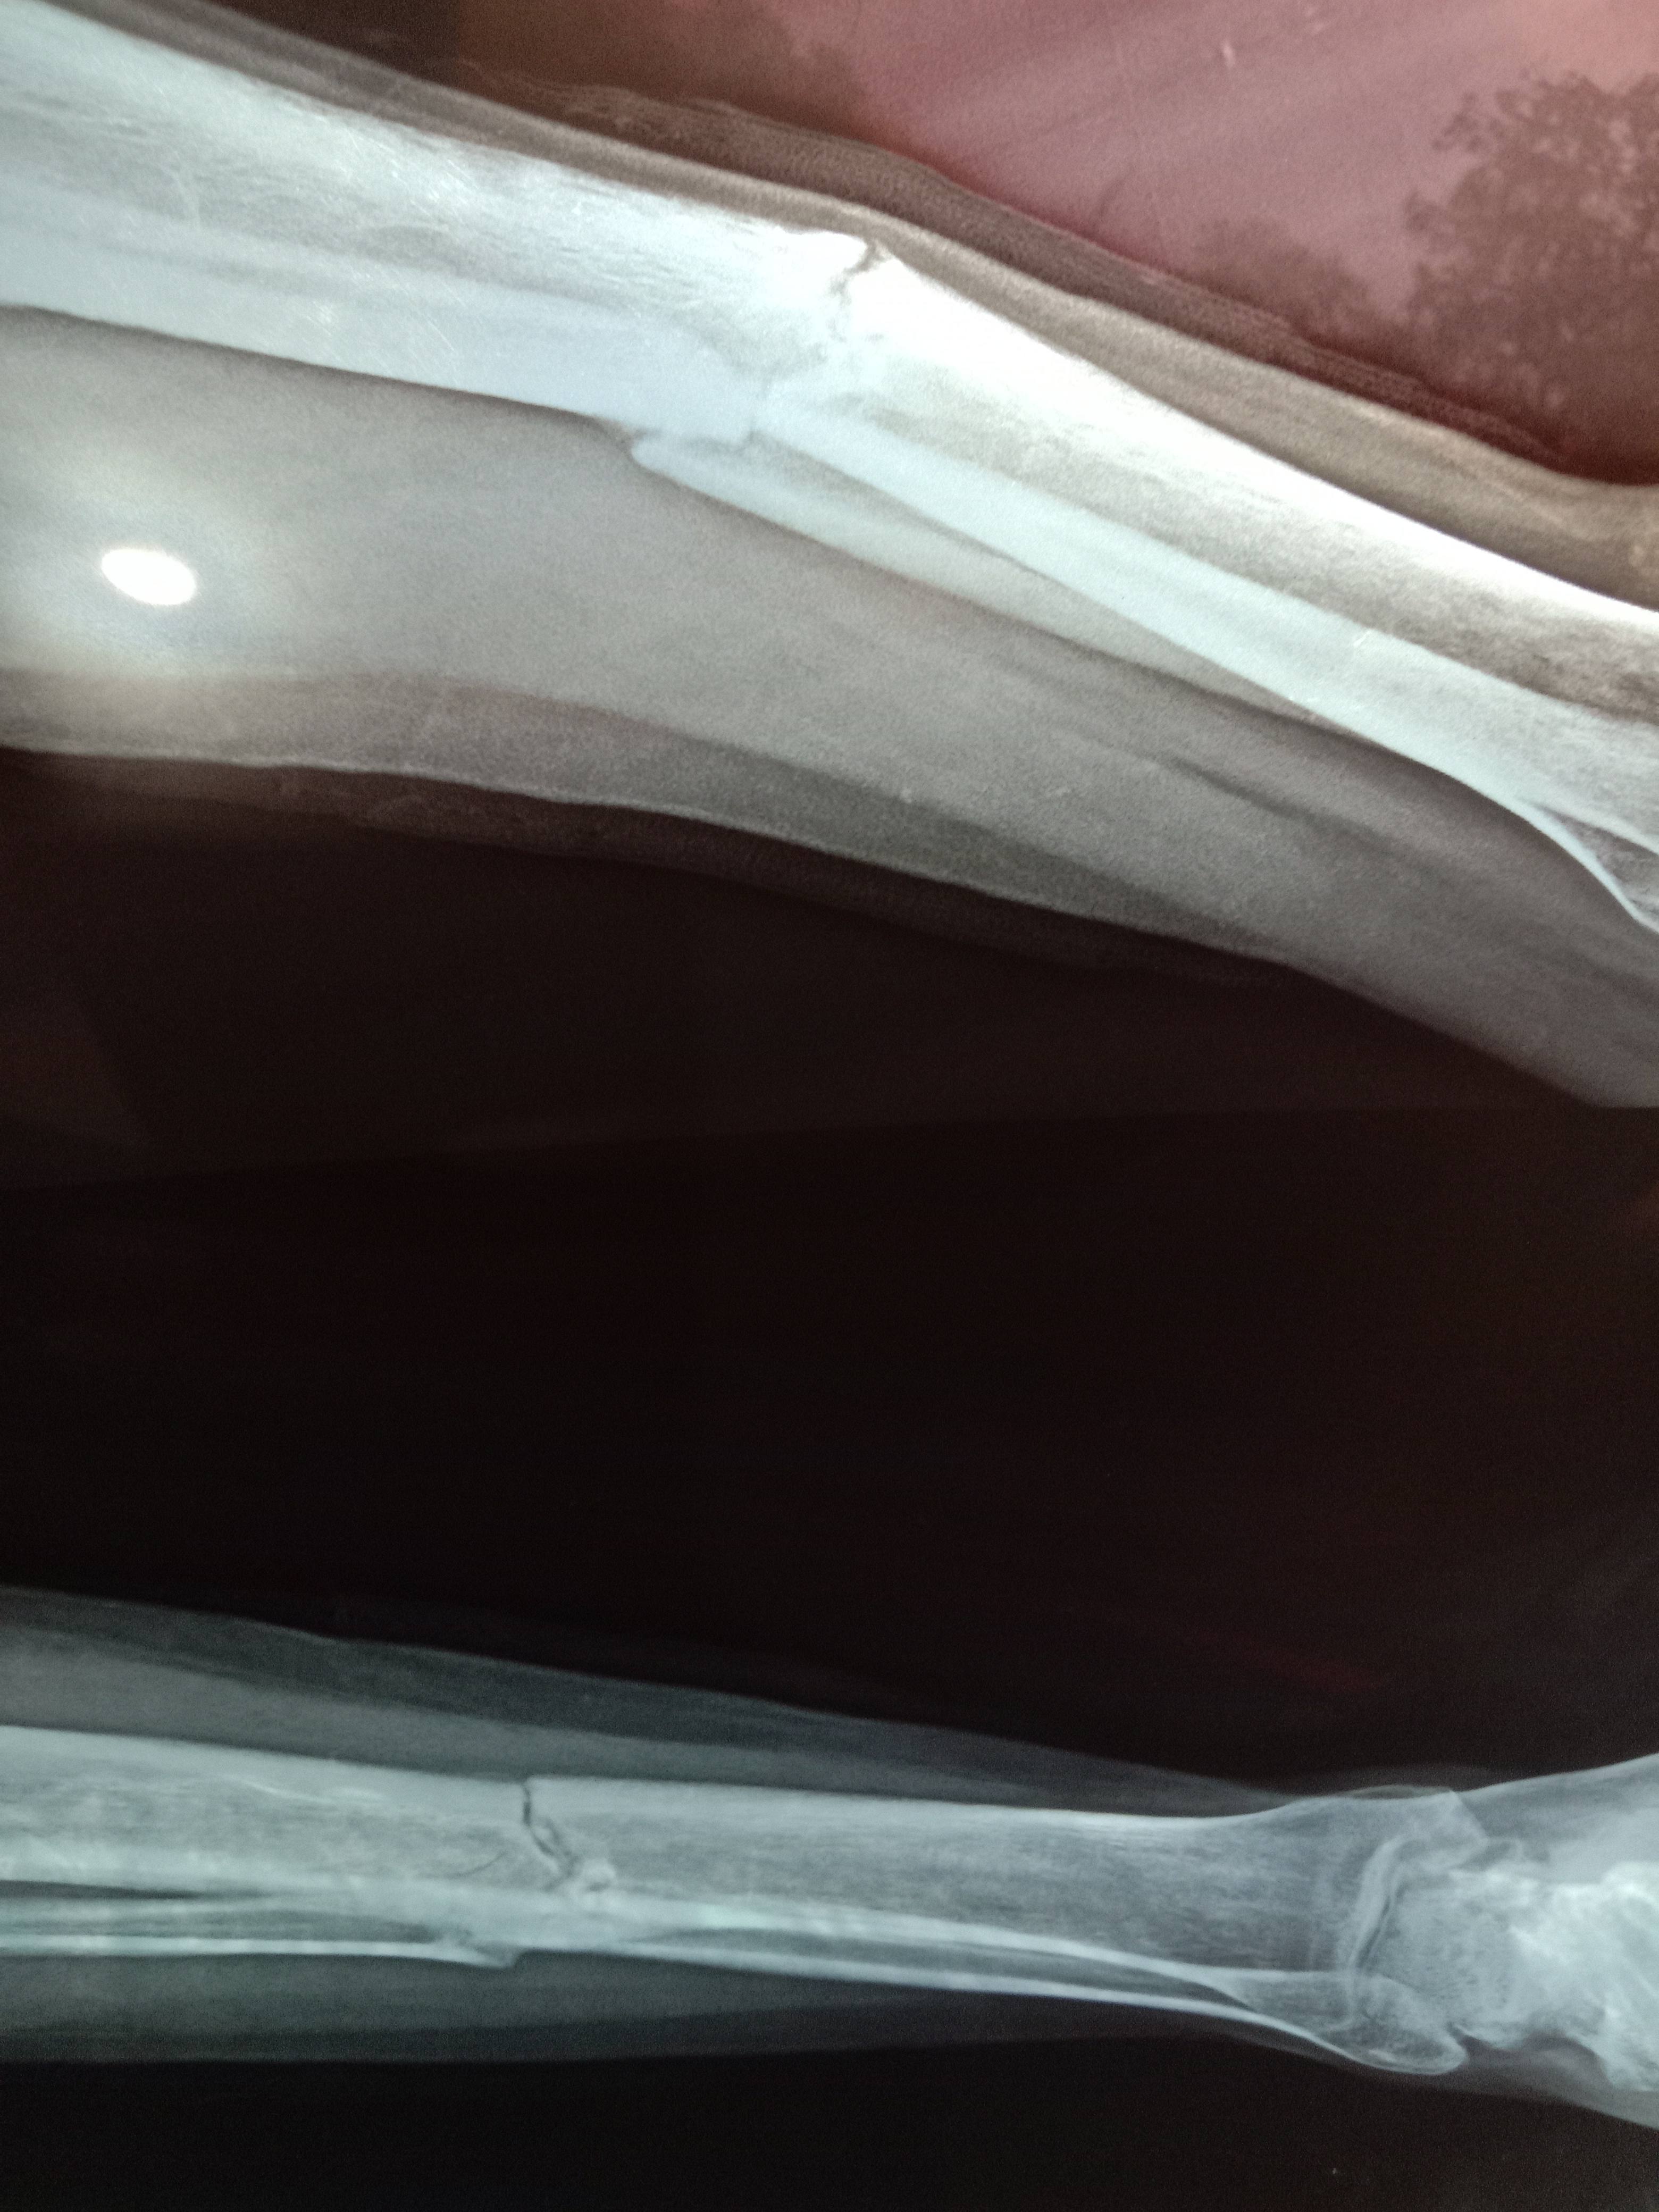

my grandfather had hip fracture ? can it unite without surgery.

Hip fracture can be onf many types. Most of the time they are classified in two types. One is intertrocahntric fracture and other is neck femur fracture. In inter trochantric fracture most of the time bed rest is sufficient. If your ftracture is very bad then that time surgery is needed. You can plan treatment with your dr ou share x rays with us.

If your fracture is neck femur fracture then that time surery is must and there is non other treatment apart from that. Neck femur does not unite and most of the time patient need hip replacement surgeyr for it.